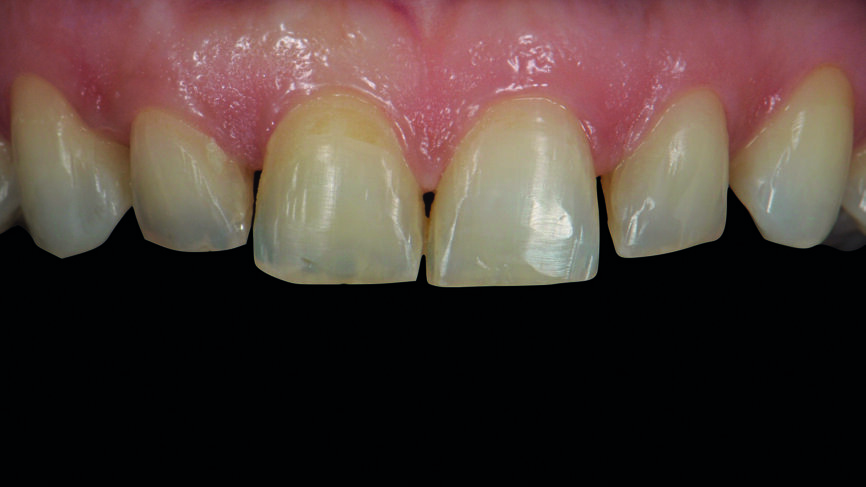

Fig. 2a : Dents antérieures après le traitement orthodontique.

Fig. 2b : Dents antérieures après le traitement orthodontique

Le traitement orthodontique proposé visait à un alignement plus favorable des dents de façon à ne requérir qu‘une préparation minimale pour la pose des facettes et à réduire le recouvrement incisif. Une année après le traitement, la patiente est revenue pour la restauration prothétique définitive (Figs. 2a et b).